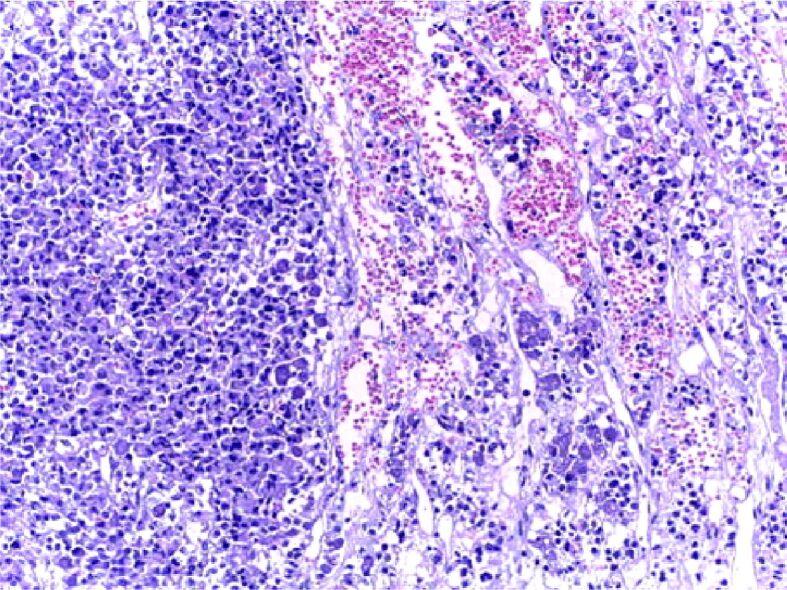

This is a narrative review of literature introducing somatostatin receptors (SSTRs) as part of understanding the somatotroph cells since they are positive in normal cells but also in tumoral cells as seen in somatotropinoma, a growth hormone (GH)-producing neoplasia, which causes acromegaly. They are five subtypes of SSTRs (1 to 5), which are immunohistochemically positive in different proportions in somatotropinomas. SSTR types 2 and 5 are most frequent in GH-secreting adenomas and they are both targeted by medical therapy with somatostatin analogues (SSTAs) like first generation Octreotide and Lanreotide (mainly targeting SSTR2) and second generation Pasireotide (with highest affinity for SSTR5), thus heterogeneous SSTRs configuration into the tumor explains different pattern of response to treatment and it might predict it once the SSTRs immunostaining is performed. Monoclonal antibodies are used for immunohistochemical detection of SSTRs; currently, a lack of standardization is presented, and scoring systems, such as Volante, H-score or human epidermal growth factor receptor 2 (HER2)-score, are applied. Immunoreactive markers like SSTRs are the U-turn in clinical practice regarding somatotropinomas since the configuration of subtypes 2 and 5 explains the responsiveness to medical therapy like SSTA. Further achievement of disease control is imperiously necessary because acromegaly has an increased rate of morbidity and mortality.

这是一篇介绍生长抑素受体 (SSTRs) 的文献综述,旨在帮助理解生长激素细胞,因为这些受体在正常细胞和肿瘤细胞中均呈阳性,如生长激素细胞瘤,这是一种产生生长激素的肿瘤,会导致肢端肥大症。SSTR 有 5 种亚型 (1 到 5),在生长激素腺瘤中以不同比例免疫组织化学阳性。SSTR 类型 2 和 5 在分泌生长激素的腺瘤中最为常见,它们都是生长抑素类似物 (SSTAs) 治疗的靶点,如第一代奥曲肽和兰瑞肽(主要靶向 SSTR2)和第二代培高利特(对 SSTR5 的亲和力最高),因此肿瘤中不同的 SSTR 构型解释了对治疗的不同反应模式,一旦进行 SSTR 免疫染色,就可以预测这种反应。单克隆抗体用于 SSTR 的免疫组织化学检测;目前,存在缺乏标准化的问题,应用评分系统,如 Volante、H 评分或人表皮生长因子受体 2 (HER2) 评分。像 SSTR 这样的免疫反应性标志物是生长激素细胞瘤临床实践的转折点,因为亚型 2 和 5 的构型解释了对 SSTA 等药物治疗的反应性。进一步实现疾病控制是必要的,因为肢端肥大症的发病率和死亡率增加。